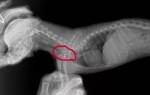

• Рентгенография (отмечают усиление бронхиального рисунка).

Для дифференциальной диагностики животному назначают рентгенологическое обследование грудной клетки с целью выявления патологических изменений.